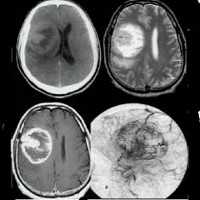

Наиболее достоверно глиома зрительного нерва диагностируется при помощи КТ головного мозга, которое позволяет визуализировать утолщенный зрительный нерв, определить границы разрастания опухоли и ее прорастание в полость черепа. При невозможности проведения КТ, используют прицельную рентгенографию черепа и рентгенографию орбиты, которые при интраорбитальной локализации глиомы выявляют одностороннее расширение полости орбиты и канала зрительного нерва, их затемнение, истончение стенок глазницы.

Наиболее приемлемым способом диагностики глиомы головного мозга на сегодняшний день является МРТ головного мозга. При невозможности ее проведения может применяться МСКТ или КТ головного мозга, контрастная ангиография мозговых сосудов, сцинтиграфия. ПЭТ головного мозга дает сведения о метаболических процессах, по которым можно судить о скорости роста и агрессивности опухоли. Кроме того, с диагностической целью возможно проведение люмбальной пункции. При глиоме головного мозга анализ полученной цереброспинальной жидкости выявляет наличие атипичных (опухолевых) клеток.